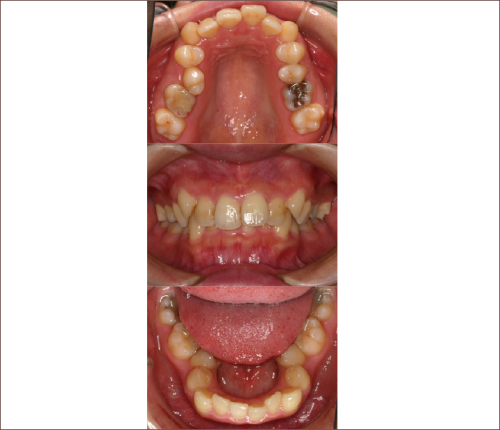

狭い歯列(狭窄歯列)によって、舌が歯列の中に収まらない状態です。

●高口蓋 ●低位舌 ●口呼吸

狭窄歯列(高口蓋)

狭窄歯列(低口蓋)

狭窄歯列(低位舌)

右のように、狭窄歯列だと舌は、狭い歯列に阻まれて、前方や上方の口蓋に自由に動くことができません。その結果、舌は低い位置(低位舌)にあり、前方に出ず後方に位置するので、気道が狭くなってしまっています。

一方、左のように、広い歯列だと舌は、前方にも上方にも自由に動けるので、舌は普段は口蓋についていて鼻呼吸が無理なくできているのです。

狭い歯列(狭窄歯列(きょうさくしれつ))

高口蓋(上顎が深い→鼻腔が狭い)

舌が歯列に納まらない→低位舌

歯並びが悪い

かみ合わせが悪い